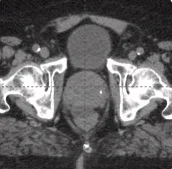

25 cc prostate post-CT showing BioProtect Balloon Spacer, prostate, and rectum. Patient received prior ADT.

Post-CT

Patient received prior ADT. Image courtesy of Dr. Stan Golin, Radiation Oncologist.